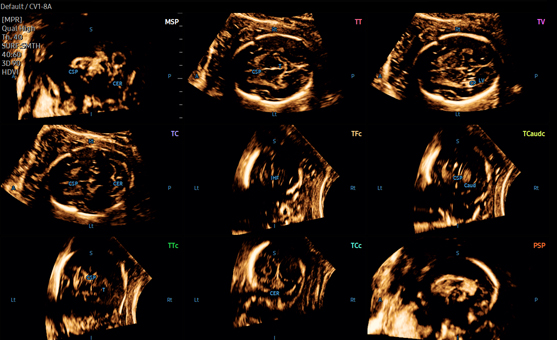

- 5D Heart Color - позволяет исследовать структуры сердца плода на предмет потенциальных нарушений кровотока, что является важной составляющей эхокардиографического исследования плода. Используя объемные данные STIC и ЦДК, строятся 9 стандартных эхокардиографических срезов плода на одном экране.

- 5D CNS+ - использует интеллектуальную навигацию, чтобы получить 9 срезов из 3 поперечных проекций мозга плода, для повышения воспроизводимости результатов и упрощения измерений. Они включают в себя аксиальную, сагиттальную и коронарную проекции с 9-ю срезами согласно международным стандартам оценки мозга плода, в соответствии с рекомендациями ISUOG.

9 стандартных видов сердца плода с 5D Heart Color